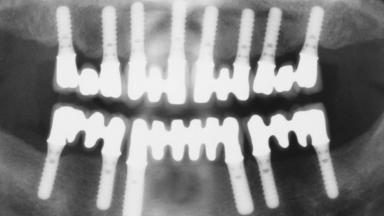

Immediate Loading of Eight Implants in the Maxilla and Six Implants in the Mandible and Final Restoration with Three-Unit and Four-Unit FDPs

# of Implants 14

Type of Implants One-Piece

Defining Characteristics Fully edentulous upper jaw to be rehabilitated with four or more implants

Modality 6+ implants with immediate loading